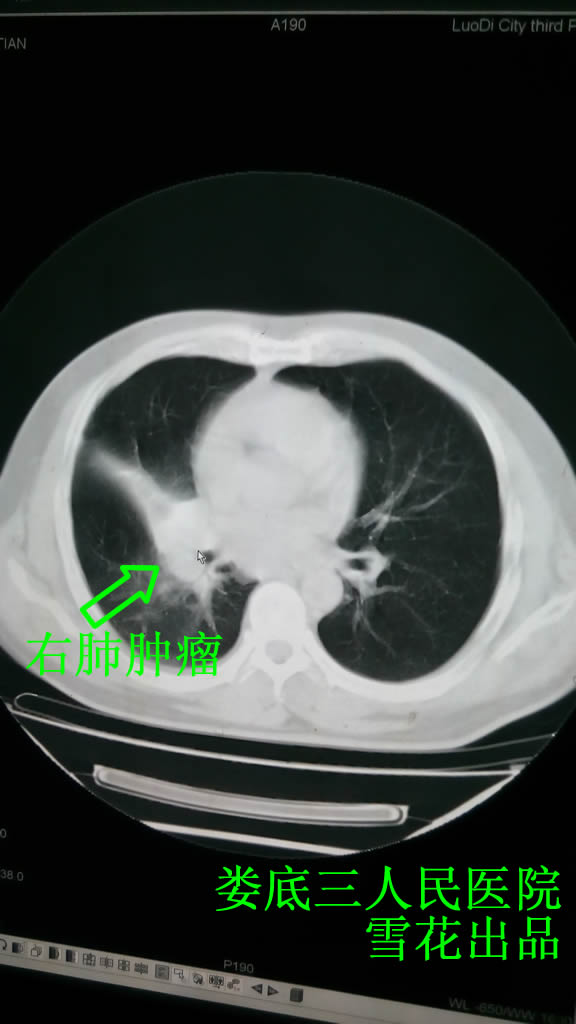

邹XX,男,47岁,因阵发性咳嗽咳痰2到湖南省肿瘤医院行肺部CT检查考虑右肺癌,行纤支镜检及活检,确诊为右肺小细胞肺癌局限期。在湖南省肿瘤医院行4周期化疗,均给予“VP-16 0.21 d-3 DDP 132mg d1”,为求放疗来我院,入院查肺部CT示:右下肺支气管狭窄并软组织,考虑中央型肺癌并右肺下叶阻塞性肺炎,右侧斜裂增厚,纵膈、腔气间隙、隆突下及右肺门多发淋巴结肿大(见图一)。立即给予右肺肿块及纵膈淋巴结三维适形放疗48Gy/16/22天,当时患者舌脉未见明显异常,但考虑到放疗可能会伤津耗气,于放疗第3天开始给予补中益气汤+滋阴润肺药物口服,每日一剂,分两次服。

放疗后复查肺部CT示右肺癌治疗后较前明显好转(见图二),患者无明显放疗反应,病情好转出院。